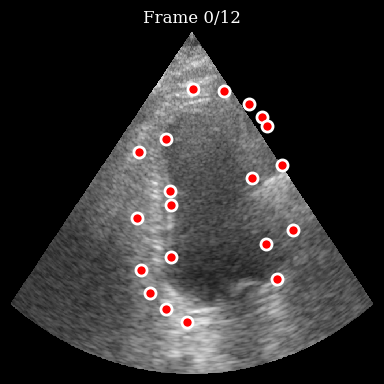

Now we can visualize the trajectories of the tracked points:

[9]:

viz_frames = []

for t in range(n_frames):

fig, ax = plt.subplots(figsize=(4, 4))

ax.imshow(frames[t], cmap="gray", aspect="auto")

for i in range(n_points):

traj = np.array(trajectories[i][: t + 1])

if len(traj) > 1:

ax.plot(traj[:, 1], traj[:, 0], "r-", alpha=0.4, linewidth=2)

ax.plot(

traj[-1, 1],

traj[-1, 0],

"o",

color="red",

markersize=8,

markeredgecolor="white",

markeredgewidth=2,

)

ax.set_title(f"Frame {t}/{n_frames - 1}")

ax.axis("off")

fig.tight_layout()

viz_frames.append(matplotlib_figure_to_numpy(fig))

plt.close(fig)

save_to_gif(viz_frames, "tracking_result.gif", fps=10)

zea: Successfully saved GIF to -> tracking_result.gif

Tracking Result